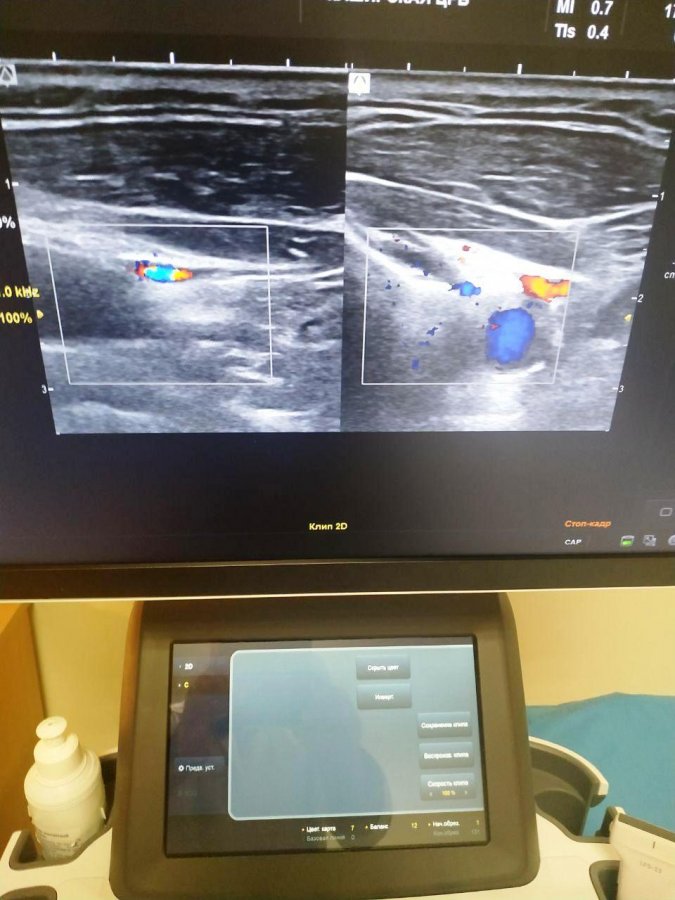

В рамках реализации национального проекта «Здравоохранение» в диагностическое отделение Каширской ЦРБ, расположенное в больничном корпусе Каширы-2, закупили новое оборудование. Это современный ультразвуковой аппарат, обладающий высоким разрешением для ультразвуковой диагностики изображений. Как уточняется, аппарат УЗИ оснащен функцией цветного доплеровского картирования сосудов. Это позволит специалистам повысить технологический уровень проведения диагностики пациентов терапевтического корпуса.